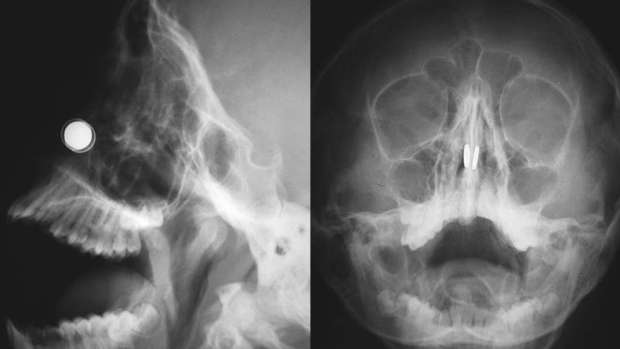

Сегодня каждый делает свой вклад в борьбу с коронавирусом. SpaceX Илона Маска производит антисептики и защитные маски. Модный дом Armani Group выпускает медицинские халаты. А австралийский астрофизик, доктор Дэниел Рирдон решил смастерить устройство, которое помогло бы людям избавиться от привычки прикасаться к лицу и уменьшило бы риск заражения коронавирусом. Однако эта затея закончилась в больнице после того, как в носу ученого застряло 4 магнита, сообщает The Guardian.

По задумке Рирдона, устройство должно было состоять из магнитов и ожерелья, которое бы издавало предупреждающий сигнал при попытке человека поднести руку к лицу. 27-летний астрофизик признался, что опыта в создании электроники у него не было. Зато у него была идея и четыре мощных неодимовых магнита. А еще Рирдону было скучно в самоизоляции, так что он решил воплотить свой замысел в жизнь.

Попытка не увенчалась успехом. Ожерелье, созданное ученым, работало с точностью до наоборот: оно постоянно издавало звуковой сигнал, отключить который можно было лишь поднеся руку к лицу. Рирдон забросил затею и стал просто развлекаться с магнитами, и тут ситуация вышла из-под контроля.